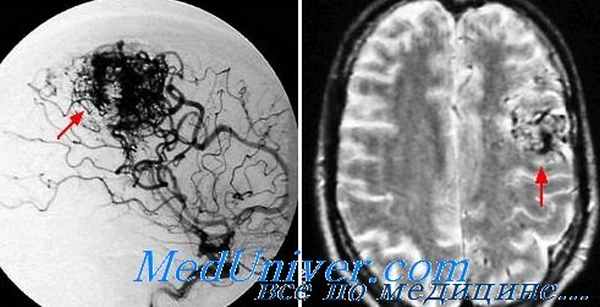

• Церебральная артериография. Этот тест считается самым лучшим способом диагностировать АВМ мозговых сосудов. Для теста в бедренную артерию вводят катетер, который достигает сосудов мозга, впрыскивают контрастное вещество, после чего делают серию рентгеновских снимков сосудов.

• Магнитно-резонансная томография. МРТ эффективнее по сравнению с КТ, если речь идет об обнаружении артериовенозной мальформации. При этом методе не применяется радиоактивное излучение, МРТ основана на использовании магнитного поля. Если перед обследованием вводится специальный краситель, «подсвечивающий» сосуды, то метод называется МР-ангиографией.

Эпиприпадки возникают у 17-40% больных с артерио-венозными мальформациями, имеющих клинические проявления. В зависимости от расположения артерио-венозных мальформаций припадки могут быть как генерализоваными (30%), так и фокальными (10%). Обычно происходит развитие тонико-клонических судорог, могут быть чувствительные нарушения в виде онемения либо парестезии. Реже возникают абсансы. Количество припадков может быть самым разным — от единичных в течение года до нескольких в течение суток.

Характерной особенностью эпиприпадков при артерио-венозных мальформациях является их стереотипность. Это наиболее выражено при фокальных конвульсиях, возникающих в одних и тех же участках тела.

Генерализованные судороги менее специфичны. Но и в этом случае можно проследить их постоянное начало в тех же конечностях, что и раньше. Часто по характеру судорожного припадка можно установить локализацию мальформации.